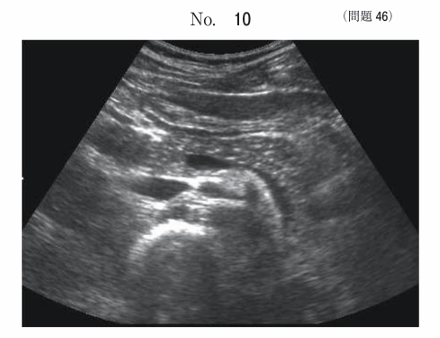

午前/問題46

膵臓の超音波画像別冊No. 10を別に示す。正しいのはどれか。

1.右肋間走査である。

2.多量の腹水が描出されている。

3.胃内に多量のガスが存在している。

4.膵の背側に脾静脈が描出されている。

5.主膵管の明らかな拡張が描出されている。